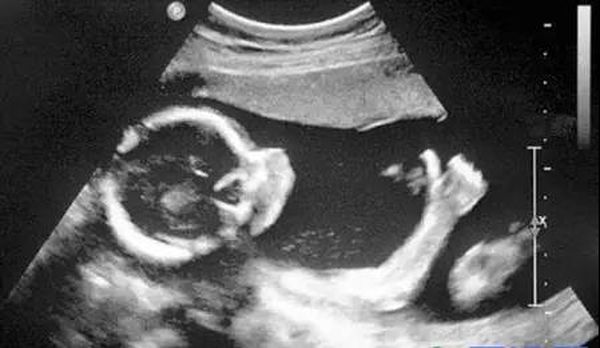

B超

像挑西瓜前敲一敲

B超的原理是用超声波穿透人体,当声波遇到人体组织时会产生反射波,通过计算反射波成像。就像挑西瓜一样,边敲边看显示病灶情况。

腹部盆腔——除肠道外,一般超声都能检查

腹腔器官受呼吸影响较大,进而影响到CT、核磁成像,而超声不会因此受影响。同时,超声对肝脏、脾脏、胰腺、肾脏、盆腔等器官诊断准确率较高。

但是超声受气体干扰很大,对于肠道等含气较多的器官,超声诊断准确率会降低。